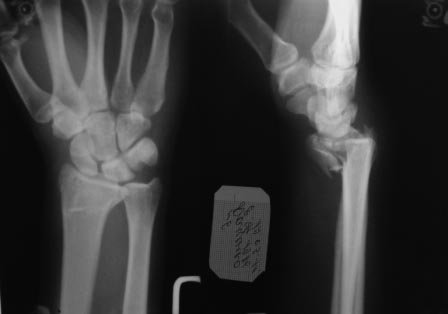

Сегодня все компании: Synthes, Stryker, Zimmer, Acumed, TriMed и т.д. имеют пластины для фиксации дистального перелома лучевой кости. На снимке метод фиксации дистальных переломов, справа Stryker, а слева пластина Synthes,

женщина 58 лет, политравма.